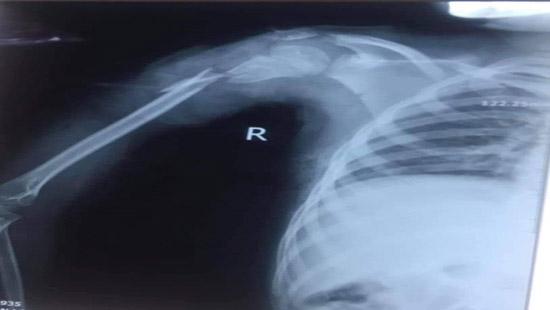

Cháu bé bị gãy xương cánh tay do va phải chân vịt thuyền thúng. |

Theo đó, chiều 13/7, bệnh viện 115 Nghệ An tiếp nhận bệnh nhi 8 tuổi (trú ở huyện Quỳ Hợp, Nghệ An), trong tình trạng cánh tay phải bị mất nhiều máu, gãy xương cánh tay, gãy xương đòn...

Gia đình cho biết, cháu bé va phải chân vịt thuyền thúng trong lúc đi tắm biển ở Cửa Lò.

Ngay lập tức, các bác sĩ đã tiến hành phẫu thuật xử trí tổn thương cho bệnh nhi. Ca mổ đã diễn ra thành công, bệnh nhi hiện tỉnh táo và có thể vận động nhẹ ngón tay, sức khỏe dần ổn định.